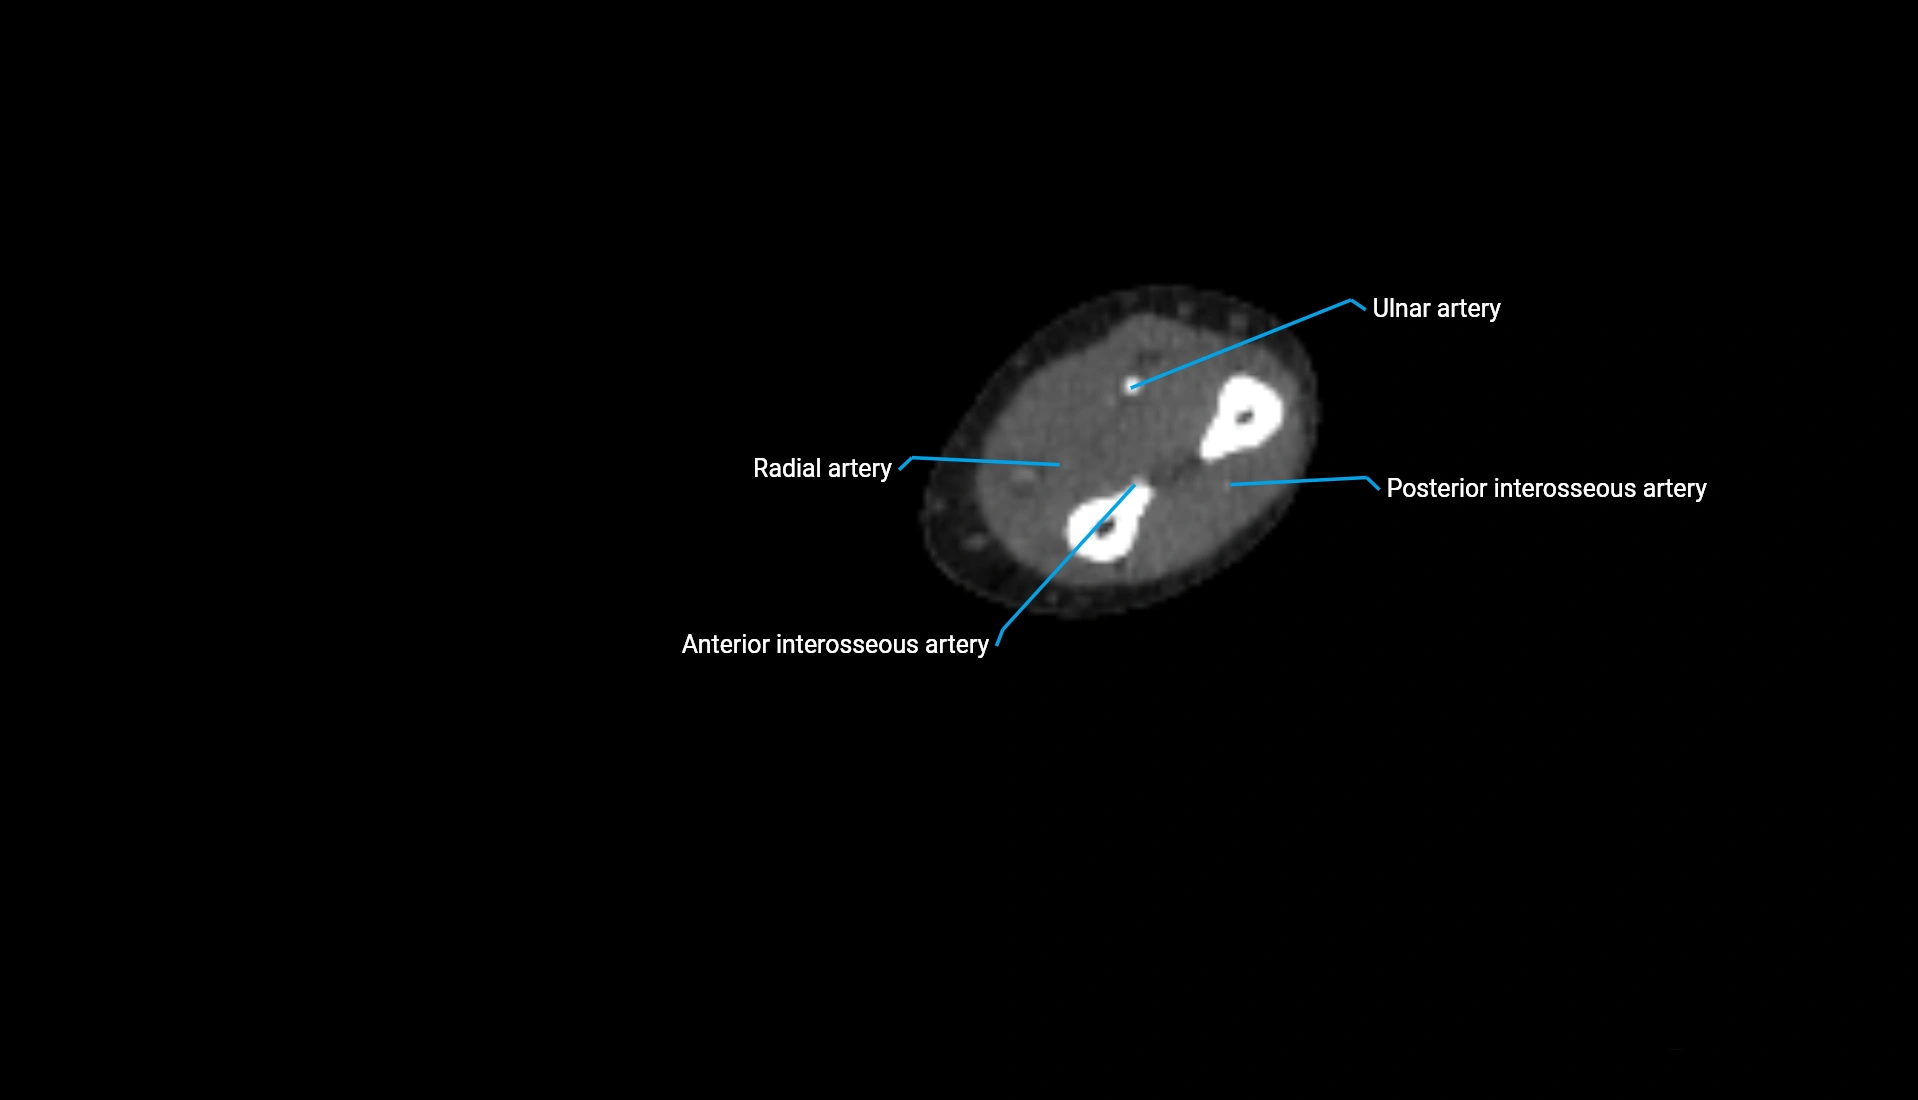

CT Appearance

Non-Contrast CT:

• Cortex: High-density, sharply defined

• Subchondral bone: Dense cancellous matrix

• Articular surface: Smooth concave contour articulating with the capitellum

• Excellent for evaluating bone integrity, alignment, and subtle fractures